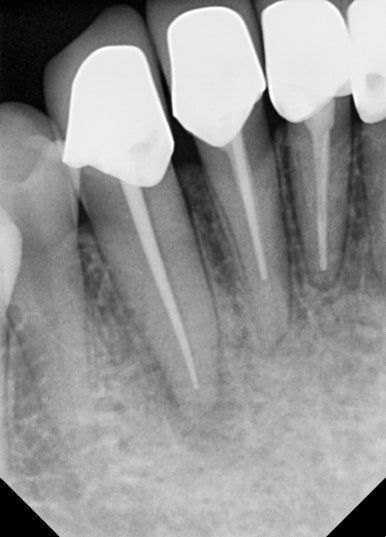

📸 케이스 5: #11, #21 앞니 Re-Endo

- 큰 염증과 통증

- 단순 재신경치료만으로는 한계가 있어

→ 치근단 수술 또는 발치+임플란트 가능성도 설명

- 반복 소독 후 염증 개선 → MTA + GP Cone 충전

✅ 크라운 재보철까지 완료